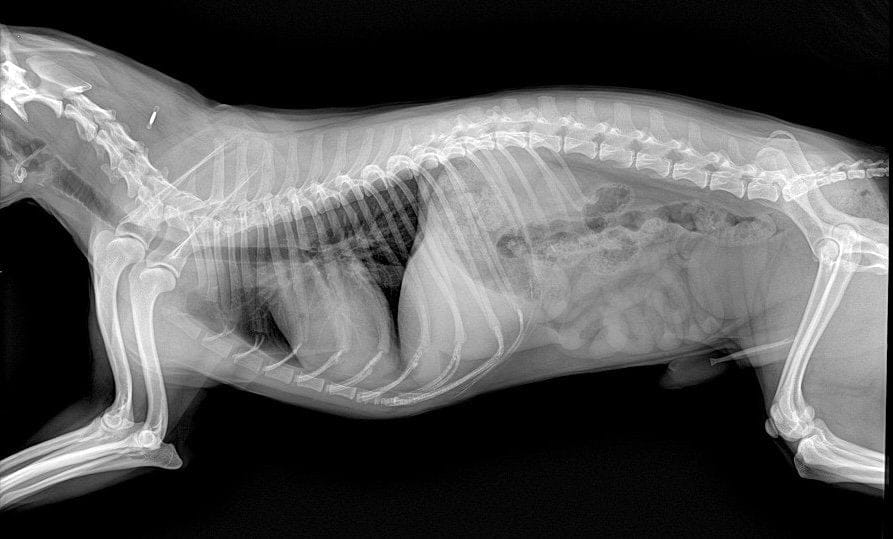

At Mavis Road Animal Clinic, we use advanced digital radiography ๐Ÿ“ธ to capture high-quality images of your petโ€™s internal structures quickly and safely. This modern technology helps us diagnose injuries, illnesses, and other health concerns with precision โ€” ensuring your furry friend ๐Ÿถ๐Ÿฑ gets the right treatment, fast.

Digital radiography is a modern form of X-ray imaging that produces instant, detailed images on a computer. Unlike traditional film X-rays, digital X-rays:

• Identify internal organ problems ๐Ÿซ€

• Locate swallowed objects or foreign bodies ๐ŸฅŽ